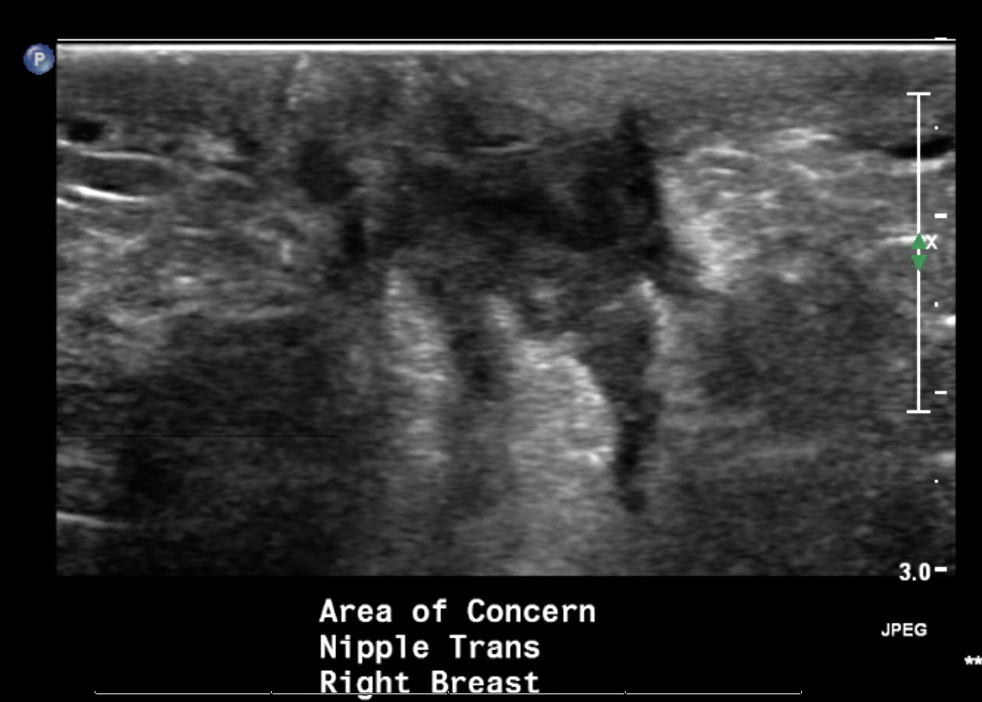

Radiology description

- Ultrasound (preferred modality): abscess shows hypoechoic lesion of purulent material, well circumscribed, macrolobulated, irregular or ill defined with septa and thick echogenic rim (Radiographics 2011;31:1683, Radiographics 2007;27 Suppl 1:S101)

Radiology images